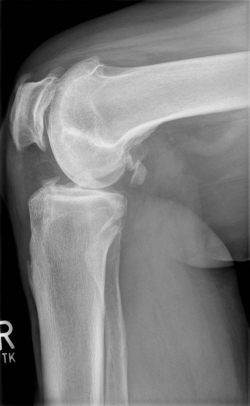

X-rays can be used to reliably diagnose the extent of joint wear. In the case of high-grade gonarthrosis, for example, the joint space and the formation of jagged edges (bone attachments, "osteophytes") as well as axial malalignment can be detected. If additional damage to the internal structures of the knee is suspected, ultrasound examination (sonography) or magnetic resonance imaging (MRI) can help clarify the situation.

Example X-ray images before and after implantation of a Persona knee prosthesis with robot.

| a) präoperative Röntgenbilder des kranken Knies in 2 Ebenen | |